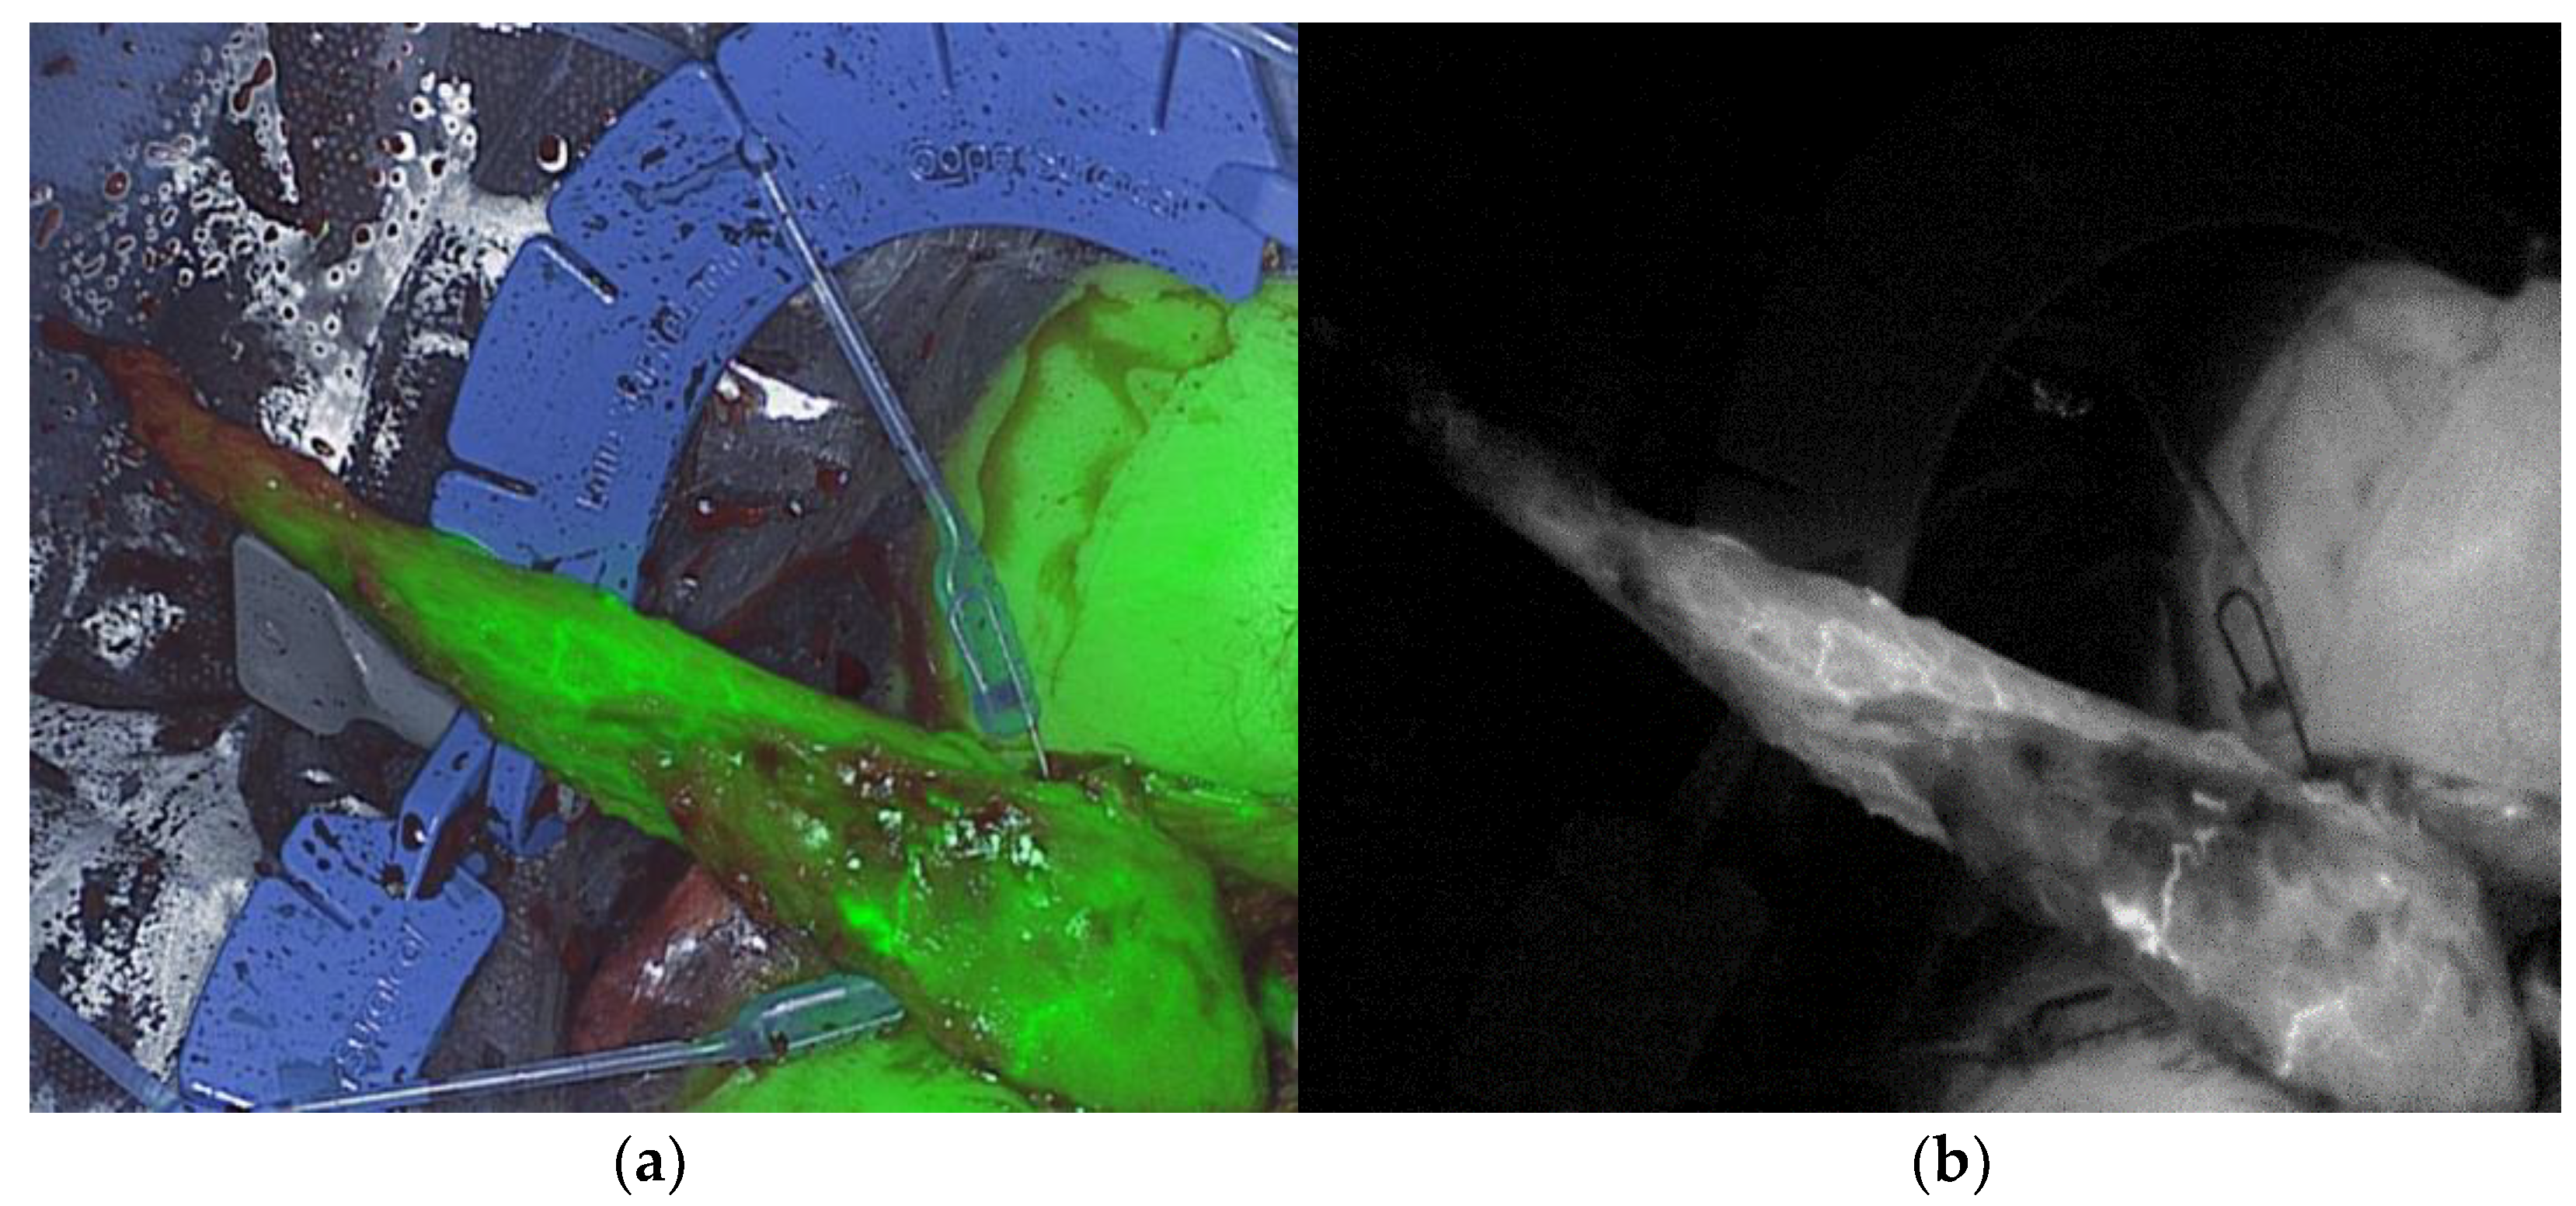

Real-time intraoperative ICG-NIRF perfusion visualization of the gracilis muscle was performed after mobilization and transfer to the perineal region, before final placement, with the Quest Spectrum® Fluorescence Imaging Platform (Quest Medical Imaging, Middenmeer, The Netherlands) equipped for open surgery (Figure 1).

Figure 1. Real-time intraoperative ICG-NIRF perfusion visualization of the gracilis muscle after mobilization and transfer to the perineal region, before final placement: (a) overlay mode of color and near-infrared real-time visualization; (b) near-infrared fluorescence mode real-time visualization.